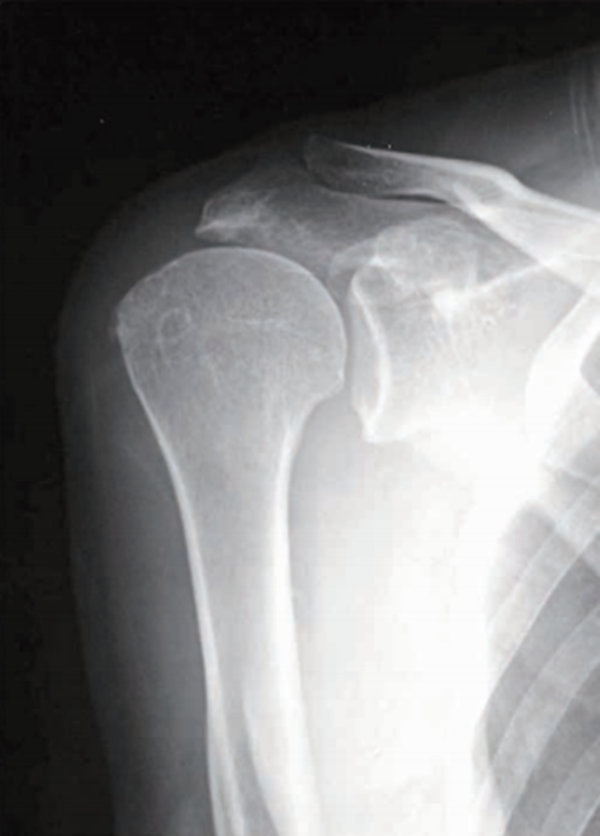

1、X线检查

X线检查用来评估肩峰形态、肱骨头和肩盂、肩峰的关系。在正位片上,大结节的硬化、增生及局限性骨密度降低,甚至囊肿形成,都是肩袖损伤的重要间接征象(图3)。

图3 大结节增生硬化X线影像